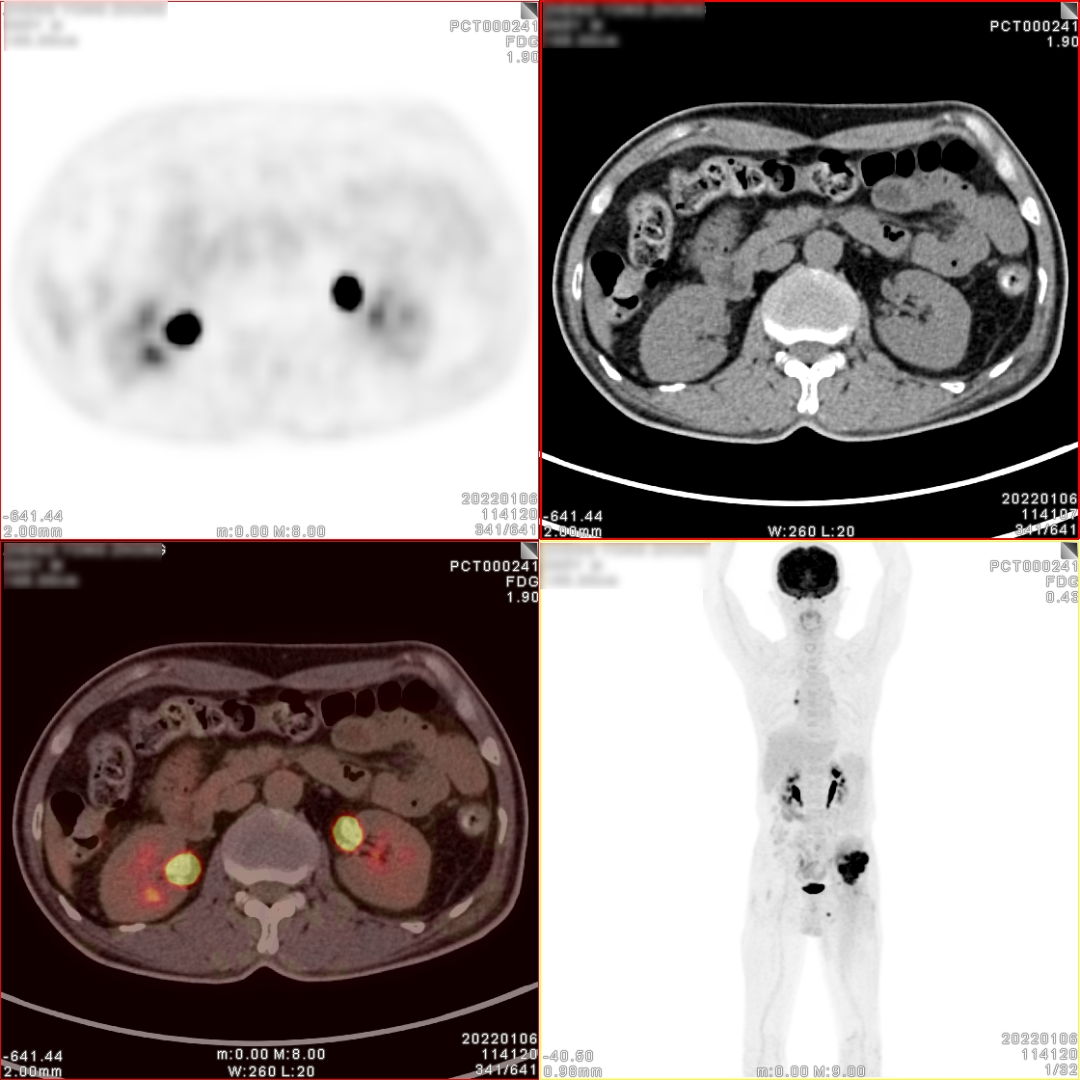

PET/CT检查图像

图片

PET/CT诊断:

3、右肺转移癌术后,右肺中、下叶支气管残端区未见明显恶性肿瘤征象;残留右肺上叶后段多个小结节影及斑片影,代谢稍增高,多考虑肺转移灶;

4、右侧肺门区肿大淋巴结,代谢增高,考虑淋巴结转移灶;